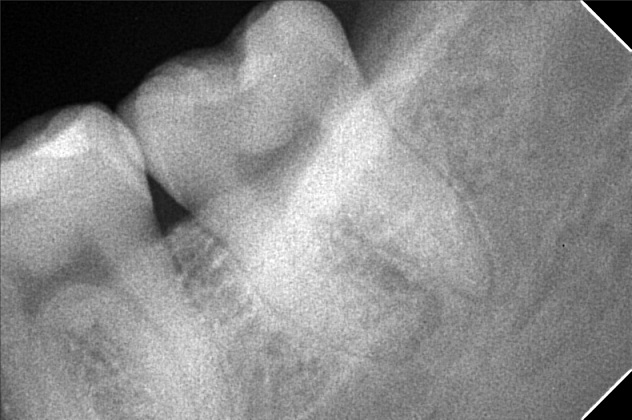

Edit Record Check our patient data records. Add patient information Patient Info Profile picture Last Name First Name Middle Name Birthdate Age Street Barangay City Country Zip Code Contact number Email Procedure 10-22-2018 > CONSULTATION ON LOWER TEETH > LINGUAL MASS #42 10-24-2018 > OP = 1,000 > GINGUAL HYPER PLAIA REMOVAL > LOCALIZED ( PYOGENIA GRAMLONA) LASER REMOVAL > LOCALIZED ON AREA OF #42 (LINGUAL) 10-30-2018 > OK GUMS AT # 42 LINGUAL STARTED TO GROW BACK 9/10/22- OP, Resto #11M, radiograph#38 02/03/2024- OP with stains request CBCT 02/17/24 check up impression 02/23/24 -sinus lift due to sinus perform -for implant #26 -double oss-1cc -cancelous bone -PRF-10 tubes -CGF-2 tubes DX: incomplete healing and bone around the synovial membrane 03/09/24 -suture removal -suture-polyglactin non-absorbable 09/14/24 recall 04/26/25 LC #35 w/ fiber CAoH,(D,O) OP File norique_ann_gonzalez.jpg File 2 img_20240309_110831.jpg File 3 img_20240405_161841.jpg File 4 File 5 File 6 File 7 File 8 File 9 File 10 File 11 File 12 File 13 File 14 File 15 File 16 File 17 File 18 File 19 File 20 Retain Record Retain Record Yes No Save Your Changes